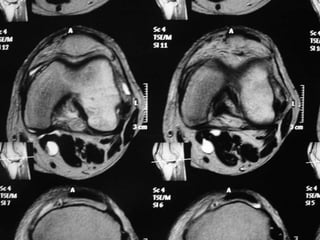

The document presents a detailed case study of a patient with transient osteoporosis of the hip (TOH) and spontaneous osteonecrosis of the knee (SONK) treated at Choithram Hospital & Research Centre in India. Over 20 years, the patient experienced multiple episodes of TOH and SONK with no history of trauma or co-morbidities, resulting in resolutions and recurrences of conditions. The information is intended for orthopedic surgery students and highlights personal experiences and case collections, with a disclaimer regarding content usage and potential controversies.